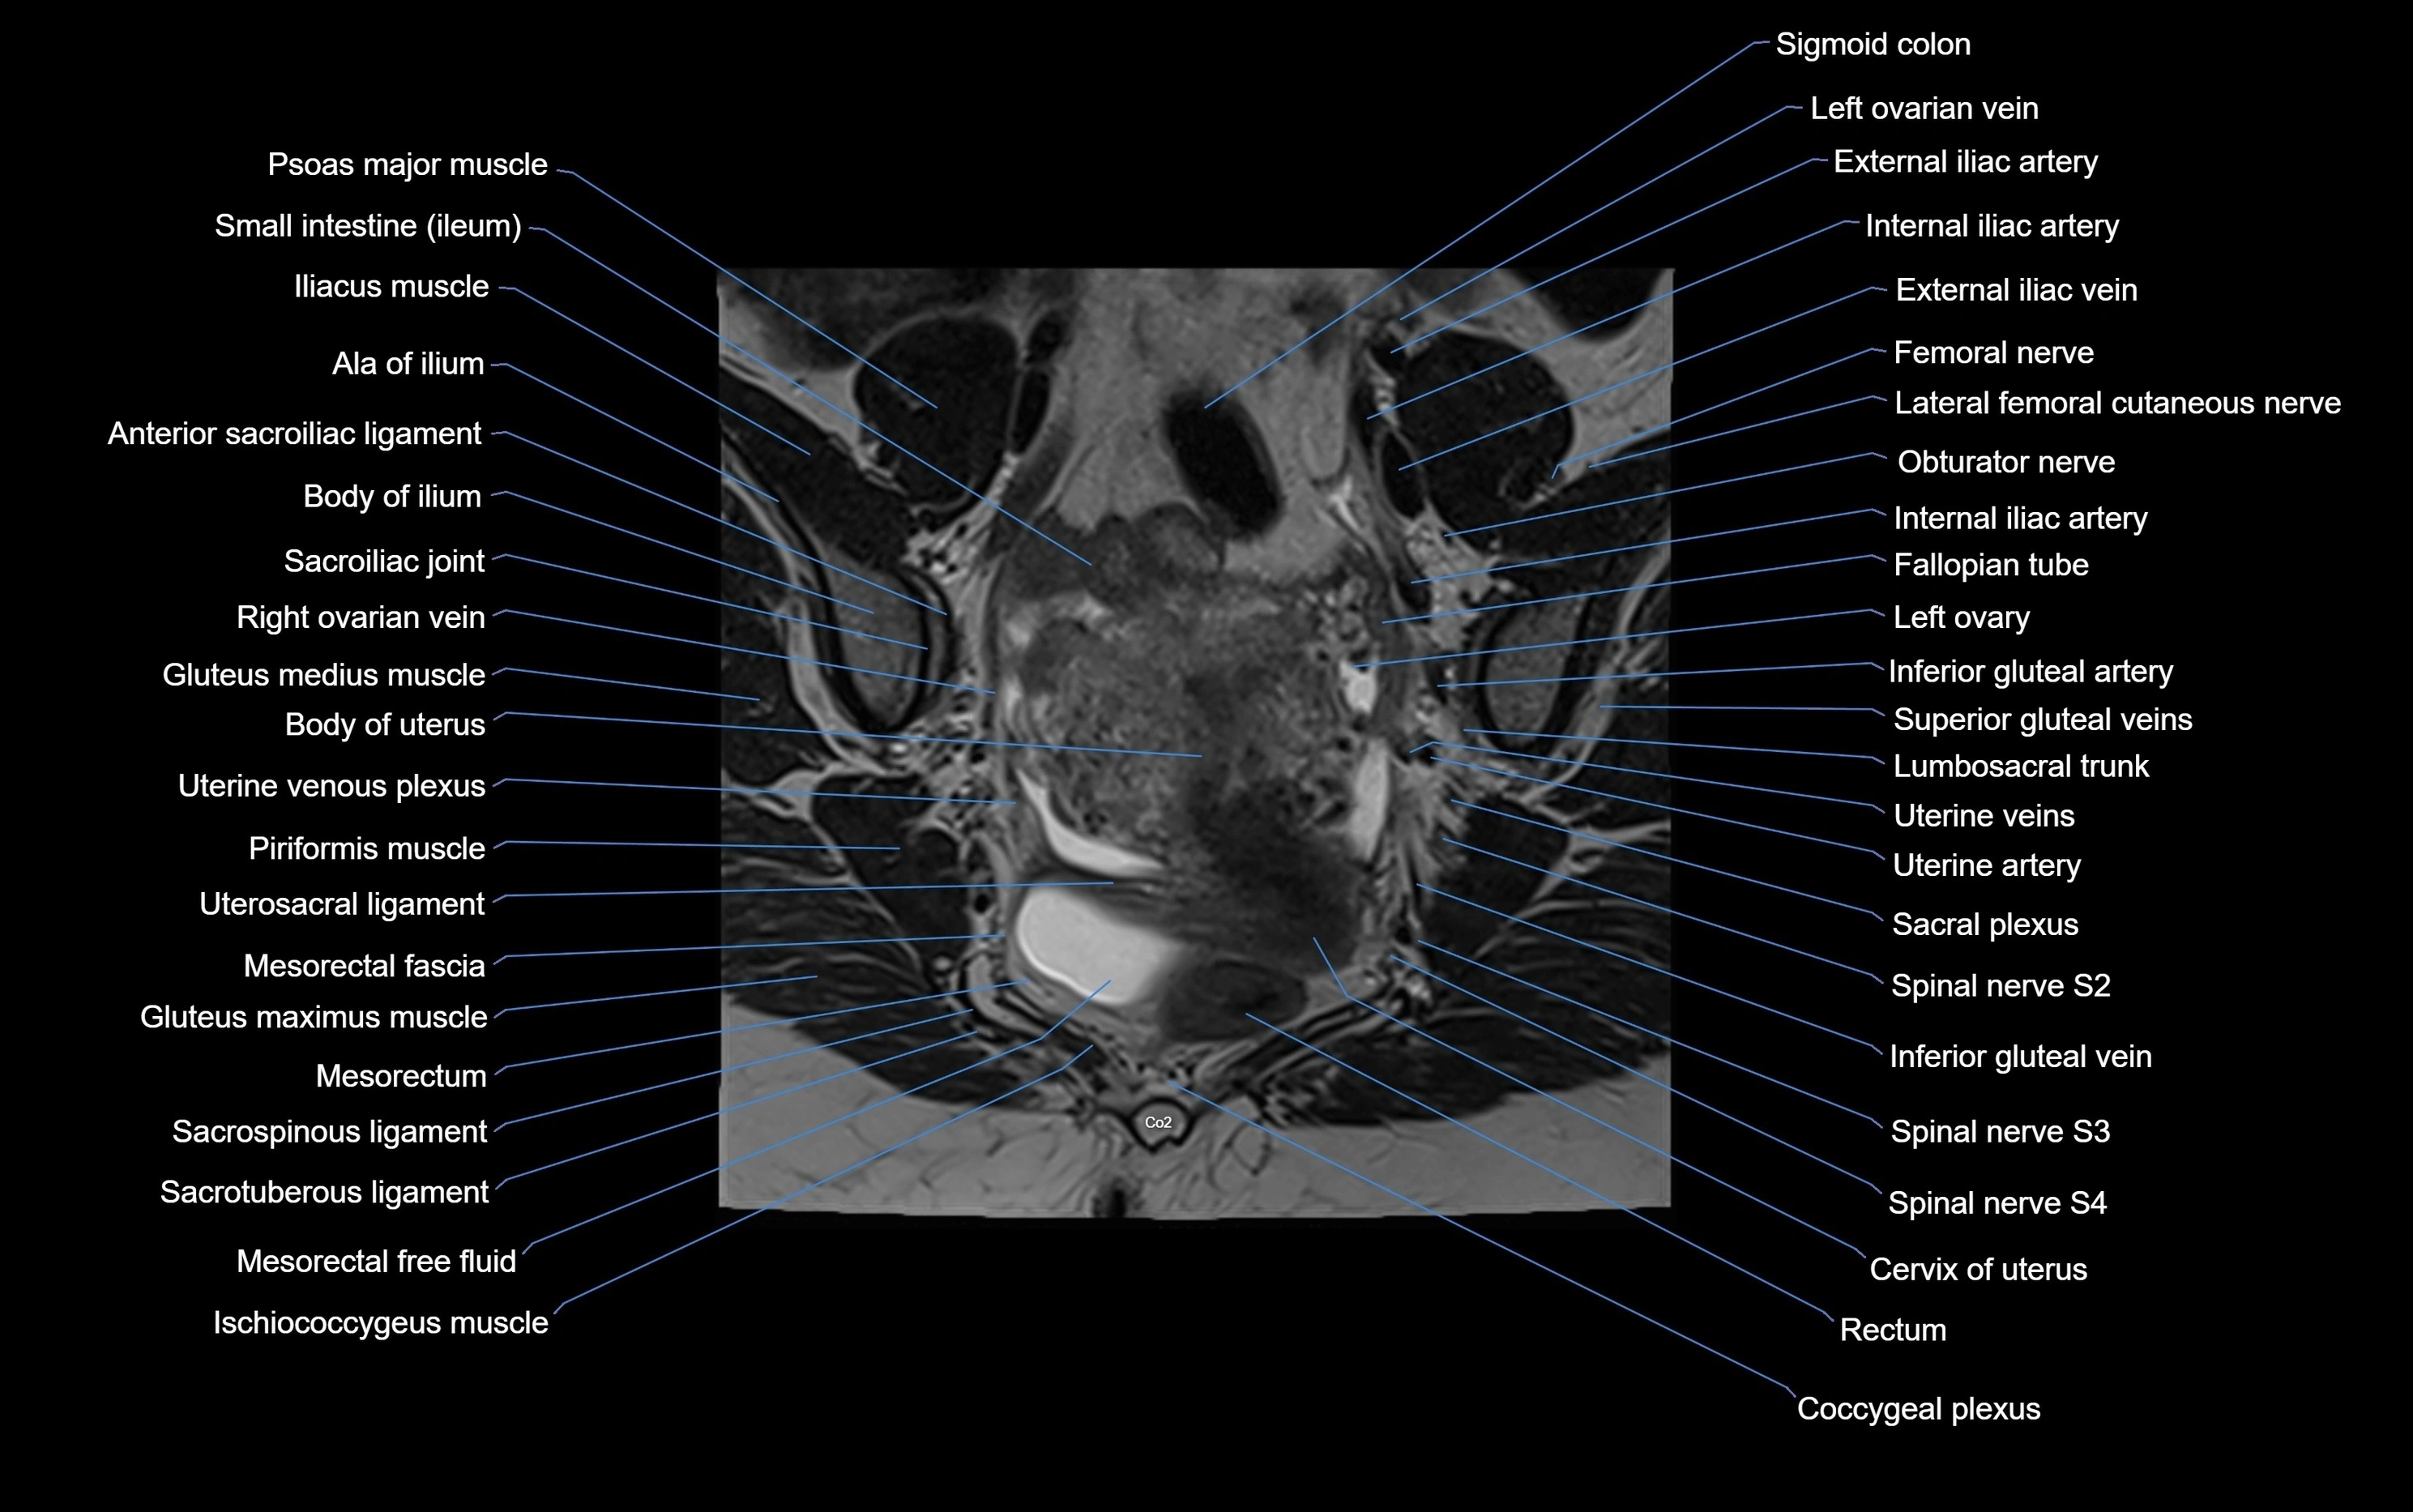

MRI image

image